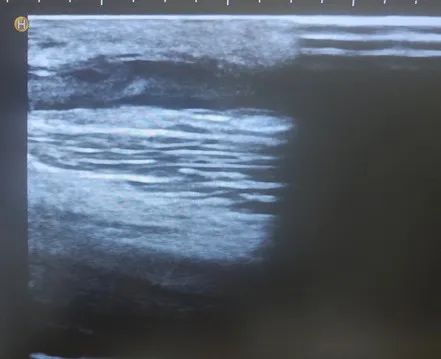

術(shù)后

董阿姨內(nèi)瘺搏動及震顫明顯

通路恢復(fù)正常

當(dāng)日上機(jī)透析治療

血流量充盈滿足透析所需